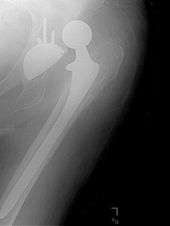

Hemiarthroplasty

Hemiarthroplasty is a surgical procedure which replaces one half of the joint with an artificial surface and leaves the other part in its natural (pre-operative) state. This class of procedure is most commonly performed on the hip after a subcapital (just below the head) fracture of the neck of the femur (a hip fracture). The procedure is performed by removing the head of the femur and replacing it with a metal or composite prosthesis. The most commonly used prosthesis designs are the Austin Moore prosthesis and the Thompson Prosthesis. More recently a composite of metal and HDPE which forms two interphases (bipolar prosthesis) has also been used. The monopolar prosthesis has not been shown to have any advantage over bipolar designs. The procedure is recommended only for elderly and frail patients, due to their lower life expectancy and activity level. This is because with the passage of time the prosthesis tends to loosen or to erode the acetabulum.[35]